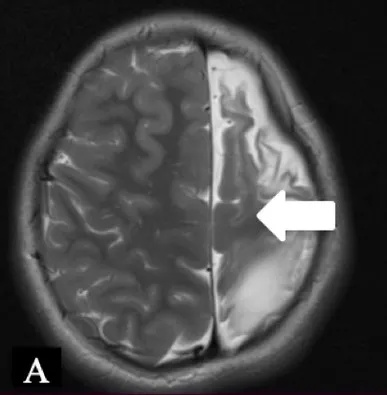

| Patient 2 | Pathology: Large cortical malformation of the left hemisphere (white oval on axial T2-MRI, Figure A1). |

|

| F, 2 years | Seizures: Daily asymmetric spasms and right hemifacial seizures | ||

| Neurological examination: Normal | |||

| Surgery: IONM during extensive frontal lobectomy up to the motor cortex; and temporal disconnection. Early postoperative axial CT scan (Figure B1) demonstrating the cystic cavity on the left frontal (bold white arrow) and small subdural hygroma with air collection (thin white arrows). | |||

| Follow-u p: No motor deficit. Early postoperative seizures with excellent effect of Carbamazepine introduction. | |||